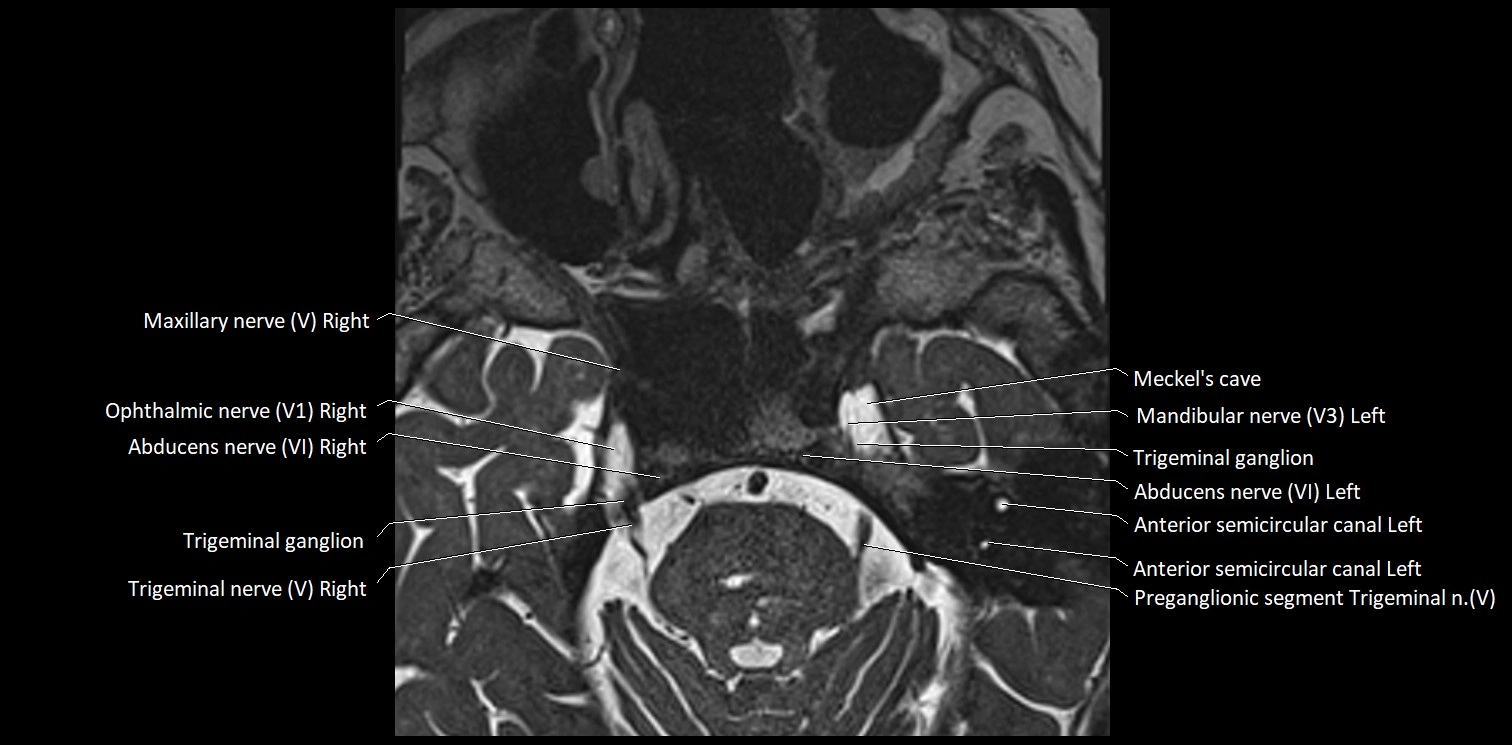

MRI Appearance

• The abducens nerve is a small, thin, linear structure

• Best visualized on high-resolution T2-weighted 3D MRI sequences (e.g., FIESTA or CISS)

• Seen as a hypointense (dark) line running from the brainstem at the pontomedullary junction, traversing the prepontine cistern, and entering Dorello’s canal under the petrosphenoidal ligament, then into the cavernous sinus, and finally the orbit

• May be challenging to visualize in standard MRI due to its small size

• Pathology may be inferred by absence, displacement, or enhancement of the nerve

MRI images

image